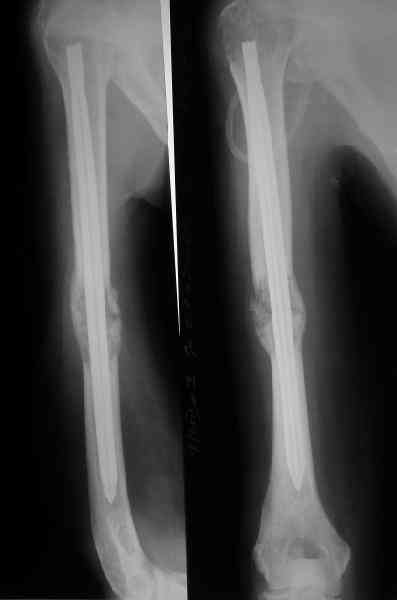

Сегодня сделали, Fixion диаметром 7,4 мм. Обе пперации продолжались по

7 мин. Картинки в приложении. Наркоз был диприваном, на спонтанном

Гвоздик 7,4 расширяется до 11 мм. Не маловато ли, судя по снимкам?